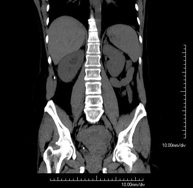

- TC Abdomen

Prova diagnòstica que consisteix en l'estudi de l'abdomen d'alta definició anatòmica (fetge, vesícula biliar, via biliar, pàncrees, melsa, estómac, intestins, ronyons, estructures vasculars, bufeta, úter i ovaris, etc.) mitjançant l'ús d'un equip de TC (Tomografia Computeritzada). Aquestes imatges s'estudien posteriorment en una estació de treball que permet obtenir reconstruccions bidimensionals en diferents plànols de l'espai i també reconstruccions 3D (volumètriques). La majoria d'estudis requereixen l'ús de contrast iodat per millorar la definició de les imatges. - TC Pelvis

Prova diagnòstica que consisteix en obtenir imatges bi i tridimensionals de la pelvis d'alta definició anatòmica (estructures òssies, estructures vasculars, bufeta, úter i ovaris, pròstata i vesícules seminals, urèters, etc.) mitjançant l'ús d'un equip de TC (Tomografia Computeritzada). La majoria d'estudis requereixen l'ús de contrast iodat. - TC Abdominopèlvic

Prova diagnòstica que consisteix en obtenir imatges bi i tridimensionals de l'abdomen d'alta definició anatòmica (estructures òssies, estructures vasculars, fetge, pàncrees, vesícula biliar, ronyons, glàndules suprarenals, melsa, intestí prim i gros, bufeta, úter i ovaris, pròstata i vesícules seminals, urèters, etc.) mitjançant l'ús d'un equip de TC (Tomografia Computeritzada). La majoria d'estudis requereixen l'ús de contrast iodat. - TC Fetge